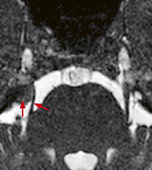

Abb. 4

Trigeminusneuralgie (Gesichtsschmerz). Das MRI zeigt ein kleines gutartiges Hirnhautgeschwulst (Meningeom, Pfeil), das den Nerv (Pfeilkopf) verlagert.